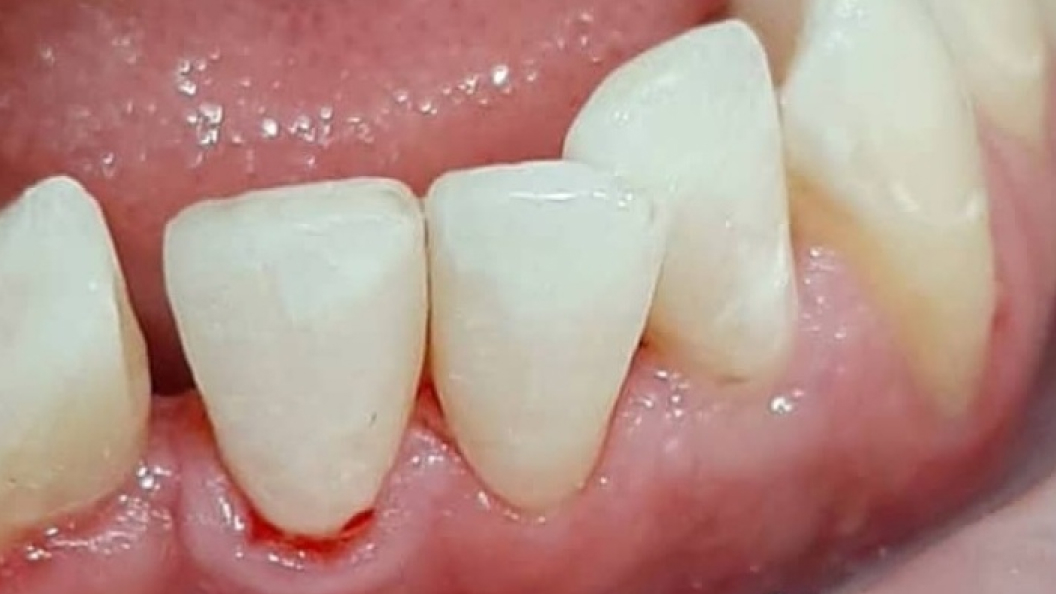

В «Стоматологию комфорта» обратилась пациентка с жалобами на эстетические дефекты 3.2, 3.1, 4.1 зубов. В процессе осмотра врач Серебрякова Мария Борисовна диагностировала хронический средний кариес зубов. Врач сделала заключение о целесообразности лечения и реставрации зуба при помощи композита Estelite.

В ходе лечения проведены следующие работы:

- введение анестетика;

- применение системы коффердам;

- механическая обработка кариозной полостей;

- медикаментозная обработка;

- наложение лечебной прокладки;

- наложение изолирующей прокладки;

- пломбирование композитом Estelite;

- шлифовка и полировка пломбы;

- обработка полости рта.